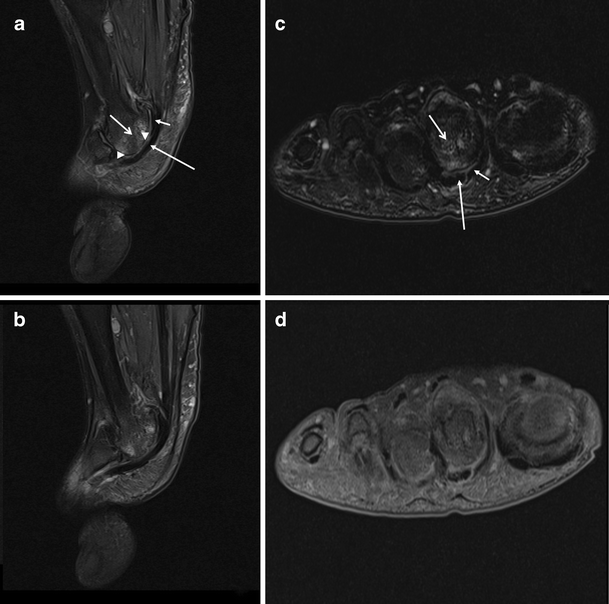

a Sagittal intermediate-weighted and b short axis T1-weighted fat suppressed images through the second MTP joint of a patient with RA showing an intact plantar plate (arrow), deep to the flexor tendon (long arrow). Small amount of high signal is seen at the insertion of the plantar plate into the proximal phalanx centrally (arrowhead), a common finding. (Cystic change is noted in first metatarsal head). c Sagittal intermediate-weighted and d short axis T2-weighted fat-suppressed images through the second MTP joint of a patient with RA. There is dislocation of the joint and the plantar plate is not visualised. There is bone marrow oedema (open arrow). On short axis section, fluid can be seen tracking from the joint around the flexor tendon sheath (arrow)